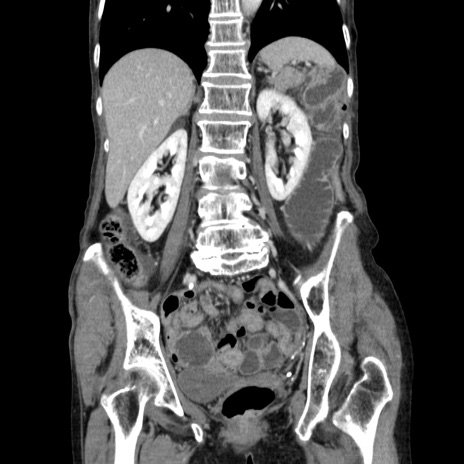

症例25(冠状断像)

【症例】80歳代女性

【主訴】胸のつかえ感

【現病歴】約9時間前に食後から胸のつかえた感じあり、嘔吐あり、来院。

【既往歴】胃癌(全摘)、胆摘、虫垂炎

【身体所見】心窩部に圧痛あり、反跳痛なし。

【データ】WBC 5700、CRP 0.05